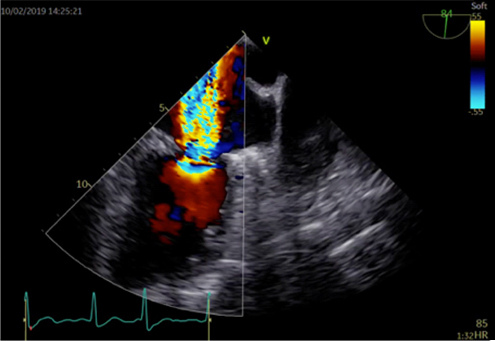

心エコー検査

心エコー検査は、超音波検査とも呼ばれ、胸に小さな機器(プローブ)を当てるだけでリアルタイムに心臓の動きの度合い、大きさ、さらには弁逆流などを診断することができます。最近は3D技術も導入され、より詳細な情報を得ることができるようになりました。

循環器診療には欠かせない、重要な検査です。当院で用いている装置はGEヘルスケア社製 VividE95が2台とPhilips社製 Affiniti 70G が2台。所要時間は20〜30分程度です。